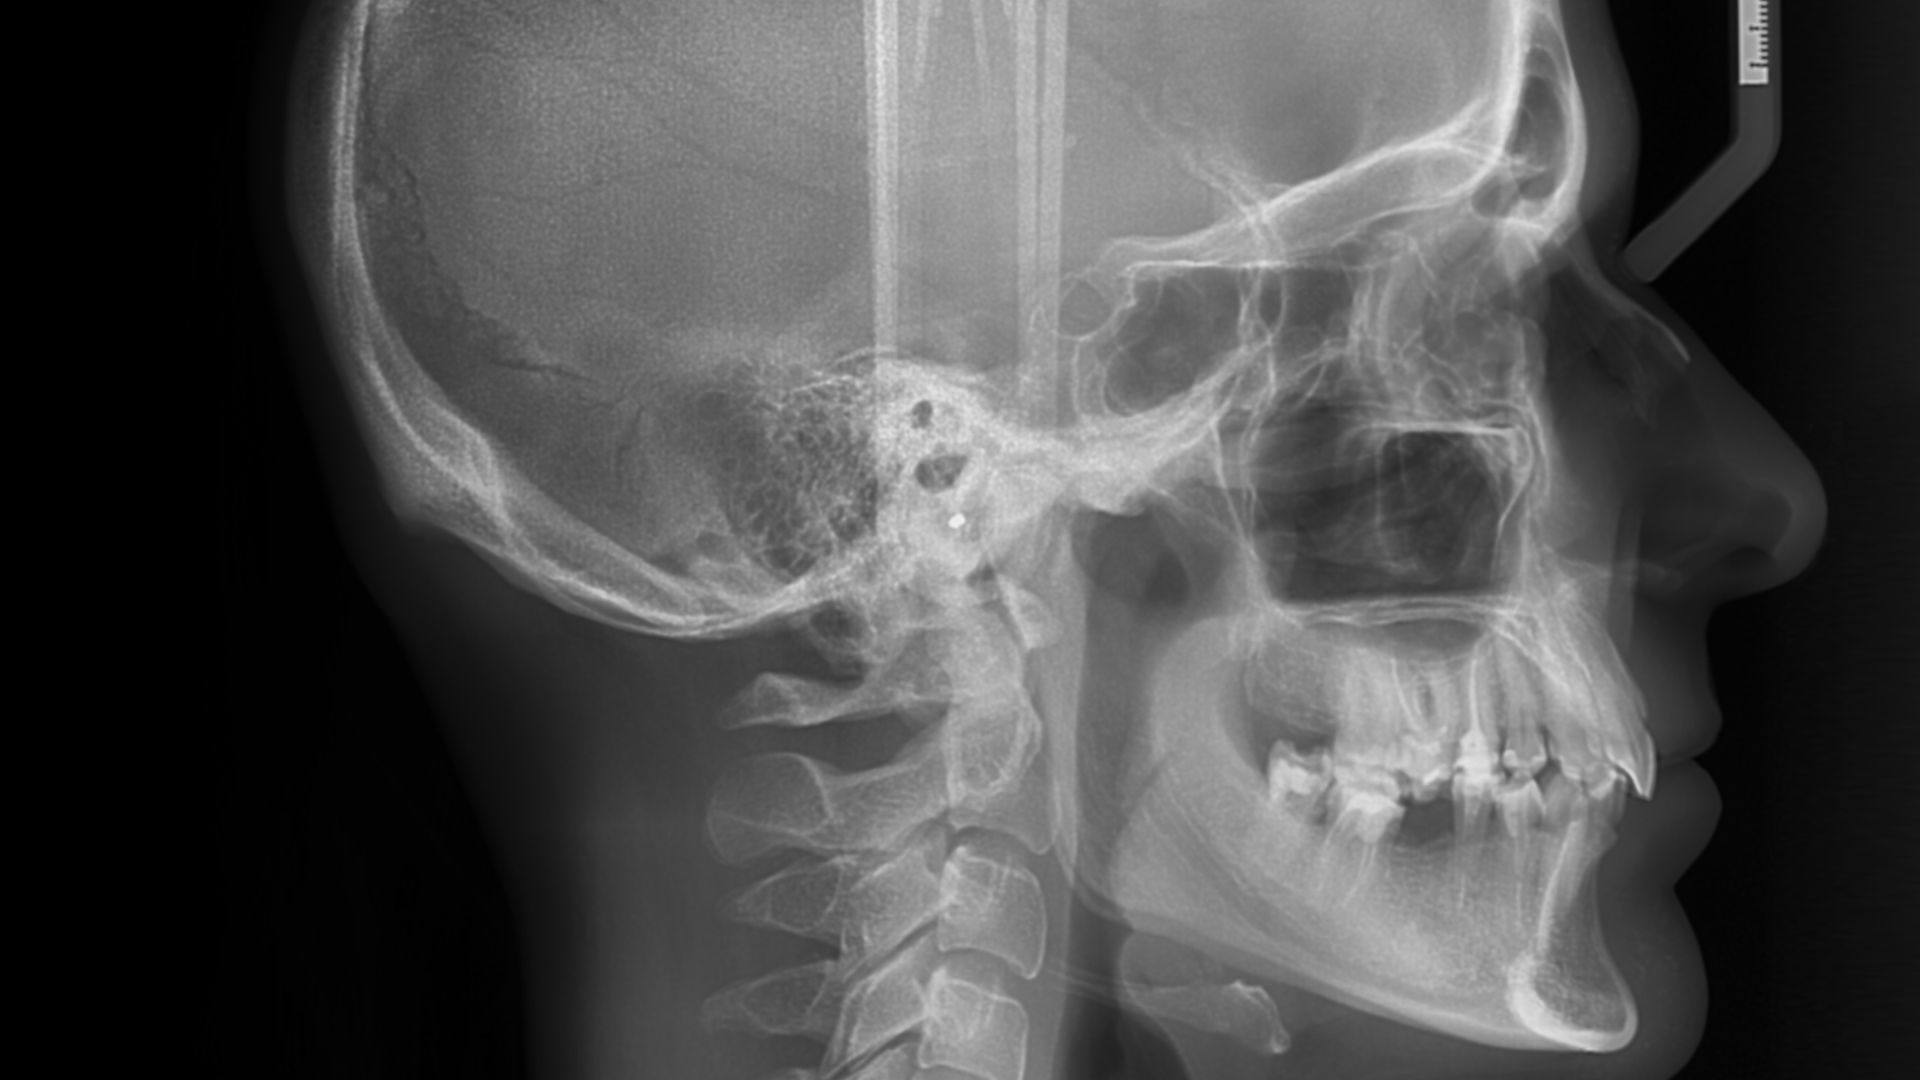

¿Planeas un tratamiento de ortodoncia? Nuestros análisis ortodónticos 2D incluyen cefalometrías, modelos digitales y fotografías estandarizadas.

¿Necesitas estudios adicionales? Ofrecemos radiografías especializadas, reportes detallados y análisis de ATM para diagnósticos completos.